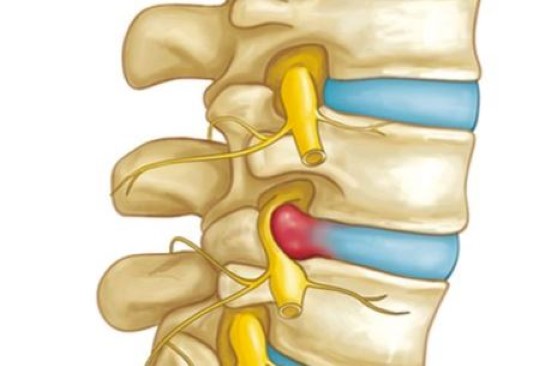

قیمت: 32٬000 تومان - دسته بندی فایل: علوم پزشکیپاورپوینت فتق دیسک کمر

فروش ویژه پاور پوینت حرفه ای فتق دیسک کمر با تخفیف استثنایی فقط 39 هزار تومان تعداد اسلاید: 16 اسلاید - زمانی که یک دیسک بین دو مهره در ستون فقرات بر روی اعصاب اطراف فشار می آورد، آن را فتق دیسک می نامند. کلمه “herniate” (her-nee-ate) به معنای بیرون زدگی یا چسبندگی است. گاهی اوقات به آن دیسک قطع شده